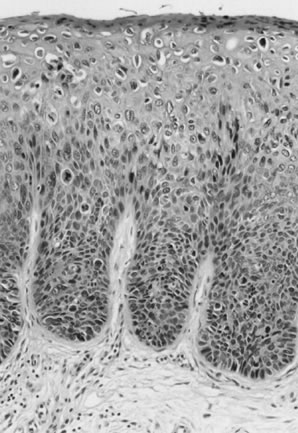

Microscopic features include a papillomatous lesion with some loss of epithelial maturation from the basal layer to the granular zone (Fig. 1). Basal and parabasal hyperplasia are usually present with accentuation of the intercellular bridges of the keratinocytes. Individual cell keratinization, dyskeratoses, and increased mitotic figures of normal morphology and location may all be present in varying degrees. Also seen are distinctive koilocytes, which are keratinocytes with distinctive perinuclear clearing and enlarged nuclei that may be hyperchromatic.

Fig. 1. Flat condyloma acuminatum/vulvar intraepithelial neoplasia (VIN) 1. There is lack of maturation in the lower one third of the epithelium and maturation with koilocytosis in the upper epithelium.

The histologic grading of VIN is determined by the degree of maturation loss of the epithelial keratinocytes (see Table 1) as follows1,2:

VIN 1: Loss of maturation, with nuclear hyperchromasia and disordered maturation, confined to the lower one third of the epithelium (Fig. 1)